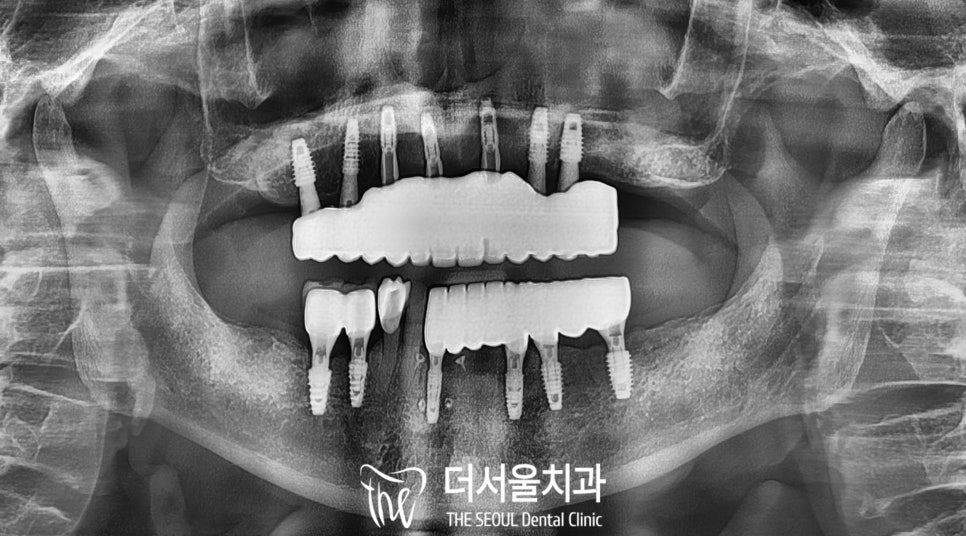

4. 디지털 풀아치

디지털 풀아치로는

성남 분당에서 최다시술을 한 곳이

바로 저희 더서울이 아닐까 싶습니다.

환자의 구강 상태를 파악한

자료를 토대로

최소 개수의 픽스처를

식립한 모습입니다.

디지털 풀아치를 이용하면

컴퓨터 프로그램 내에서

초기고정력을 잘 얻을 수 있는

치조골의 위치를 알 수 있기에

식립 당일 임시 틀니를

장착해드릴 수 있습니다.

그러면 환자는 자고 일어났더니

임플란트 수술도 끝나있고,

식사를 할 수 있는

임시치아까지 생기기에

만족도가 높은 좋은 방법입니다.

상대적으로 골질이 물러

잇몸뼈와 결합되기까지 시간이 좀 더 걸리는

상악을 우선으로 진행하고,

이어서 하악까지 안전한 식립을 해드린 모습입니다.

이후에는 이렇게 임시틀니 상태로

몇개월정도 골유착이 되기를 기다렸다가

적절한 고정력이 나오면

최종 보철을 연결해드리는데요,

보철의 교합면에 있는 홀(hole)을 통해

잇몸뼈 안의 픽스처와 나사 형식으로

연결할 수 있어

틀니와 다르게 들썩거리거나

탈락할 확률이 낮습니다.